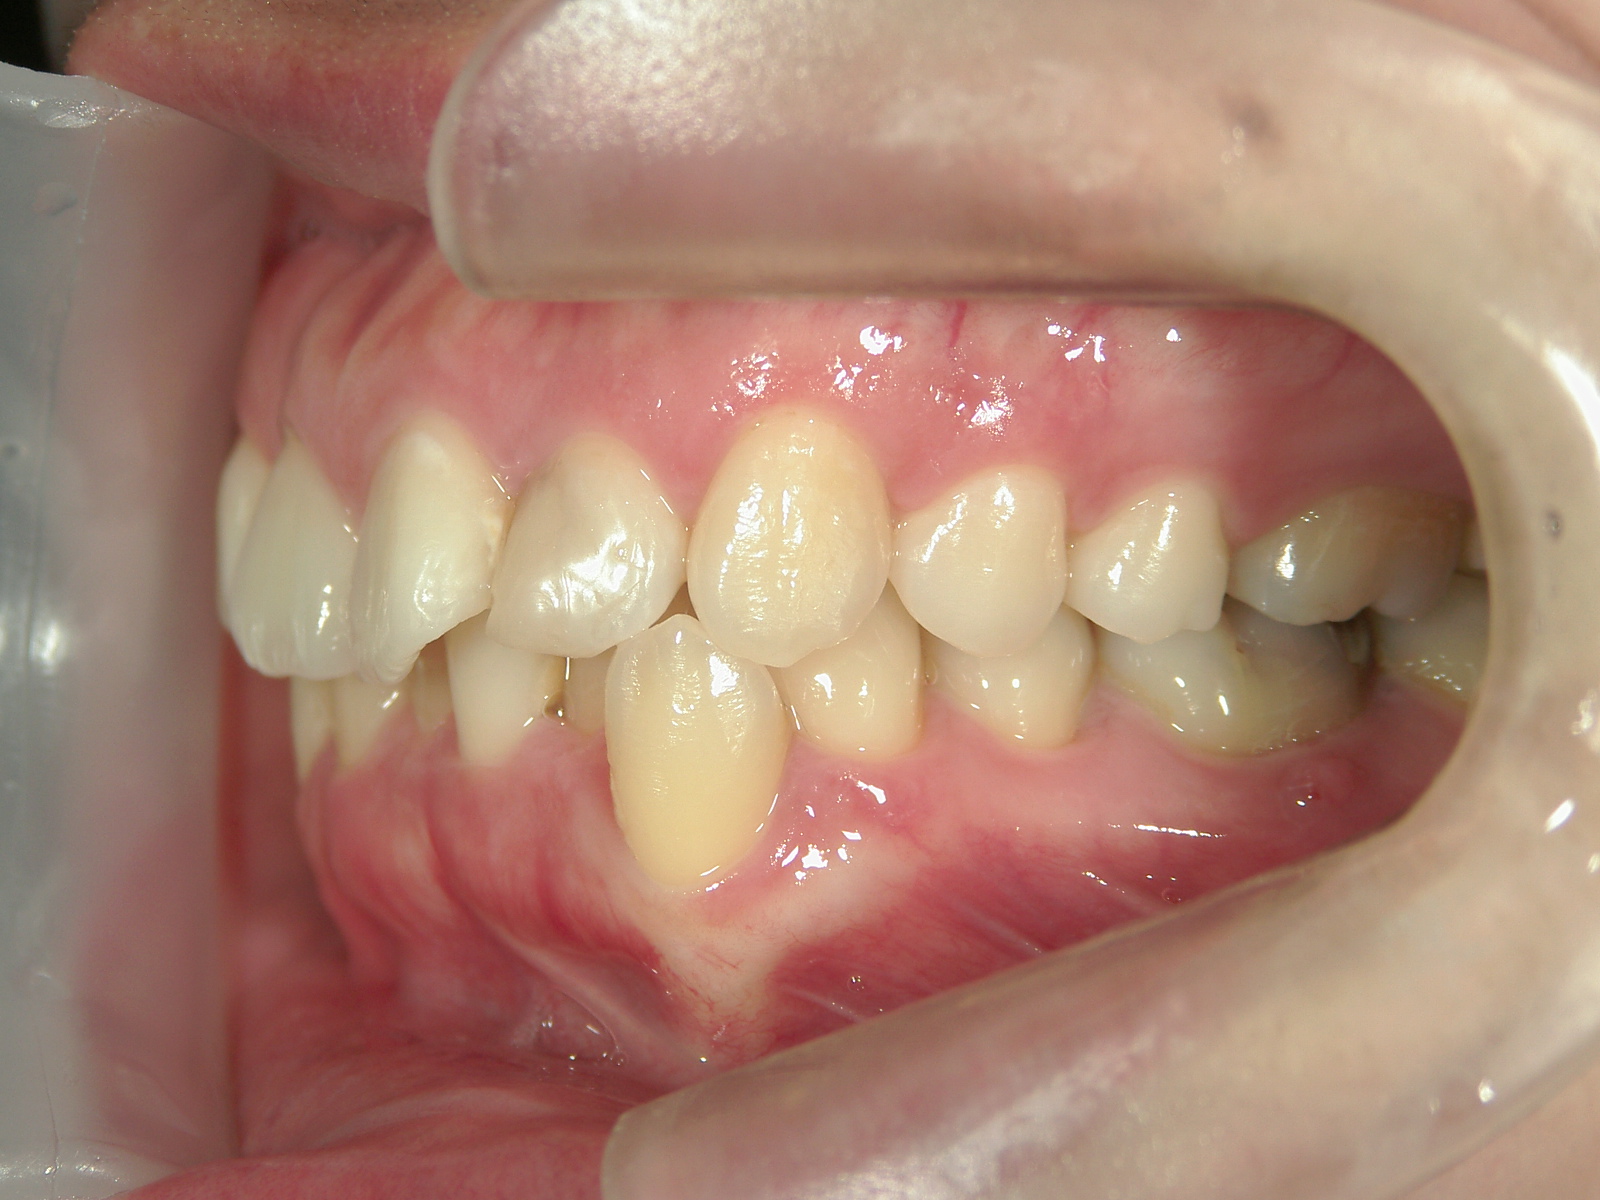

左右上 第一小臼歯(2本)、左右下 第二小臼歯(2本)を抜歯。

矯正装置(BH・QH)を併用。

ミニインプラント、アップライトスプリングを併用。

右下大臼歯(2本)をZ冠、E-MAX(On)に変更。